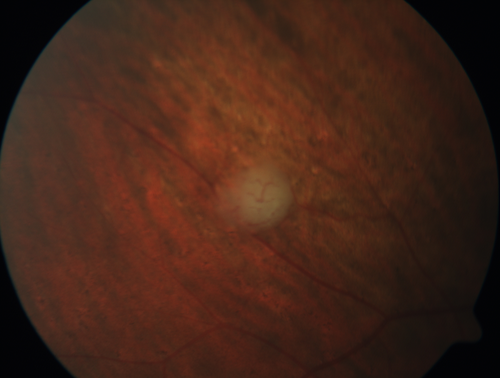

Retinal Capillary Hemangioma - Endophytic and Exophytic

46 year old female with normal vision - her father died of pancreatic cancer